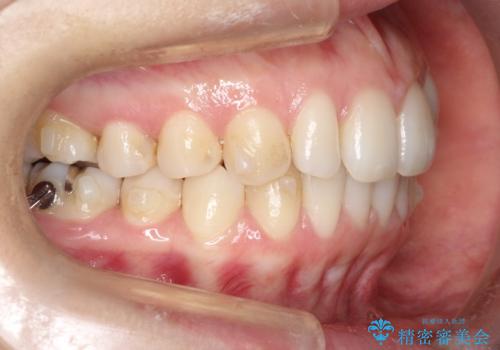

初診時の歯並びの状態としては、上下ともに前歯部の中等度のがたつきがあり、特に左上の前歯が1本内側に入り込んでしまっている状態でした。

また、2mm程度の正中離開がありました。

抜歯なし/インビザラインによるマウスピース矯正にて治療を行いました。

内側に入り込んでしまっている歯を出してくることに非常に時間がかかりましたが、一度歯を歯茎の方へ押し込みそして前へ出してくる2段階の治療を行いました。